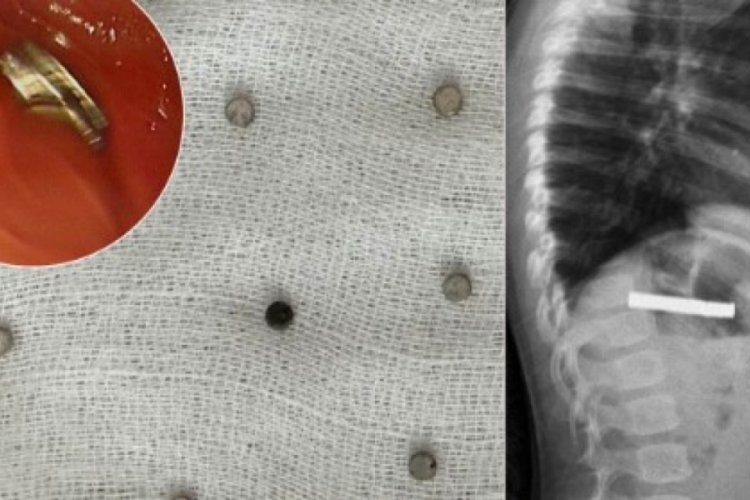

Küçük çocuğun boğazından 19 mıknatıs çıktı

Erzurum'da, henüz nedeni bilinmeyen şekilde 19 mıknatısı yutan çocuk, Elazığ'da yapılan endoskopiyle sağlığına kavuştu. Mıknatısların yemek borusu ve mide girişinde zedelenmelere yol açtığı, çocuğun tedavisinin ardından taburcu edildiği bildirildi.

Edinilen bilgiye göre, Erzurum'da bir çocuk evde bulunan 19 tane mıknatısı yuttu.

Daha sonra çocuk Elazığ'a sevk edildi. Fırat Üniversitesi Çocuk Gastroenteroloji Hepatoloji ve Beslenme Bilim Dalı Başkanı Prof. Dr. Yaşar Doğan, çocuk hastanın yemek borusuna yapışmış 19 mıknatısı endoskopik yöntemle çıkardı.

Mıknatıslar uzun süre yemek borusunda takılı kaldığı için yemek borusu ve mide girişinde zedelenmeler olurken, çocuğun sağlık durumunun iyi olduğu ve taburcu edildiği öğrenildi.